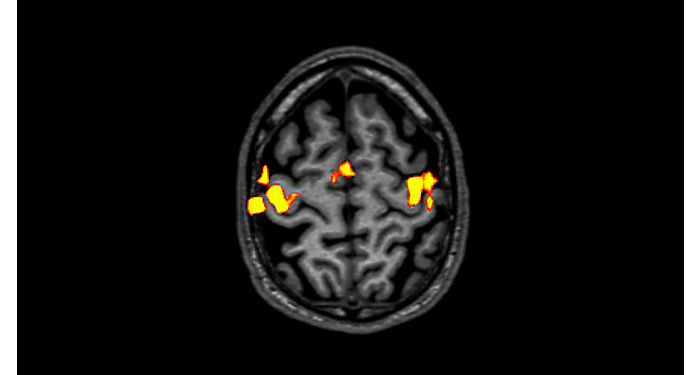

El 70% de los radiólogos consideran que las indicaciones neurológicas son un desafío, sobre todo debido a la falta de técnicas apropiadas de imagenología y visualización¹. Philips tiene como objetivo proporcionar la mejor claridad de diagnóstico posible y orientación terapéutica para todos los pacientes con trastornos neurológicos. Al aprovechar nuestra plataforma digital dStream, este año presentamos un conjunto de estrategias nuevas de imagenología y visualización. Esto puede ayudarlo a resolver preguntas sobre neurología complejas con mayor certeza, así como a desbloquear nuevos territorios neurológicos en aplicaciones neurofuncionales avanzadas. Este es un paso clave para aumentar el diagnóstico neurológico y, en última instancia, impactar más vidas con la RM. ¹ TMTG Market Survey 2016

Nuevas aplicaciones neurológicas

Trabajar en la Universidad de Vermont en el campo del desarrollo cognitivo

Richard Watts y Hugh Garavan, de la Universidad de Vermont, están hablando sobre la colaboración con Philips en MultiBand SENSE y cómo lo usan en sus protocolos de estudio.